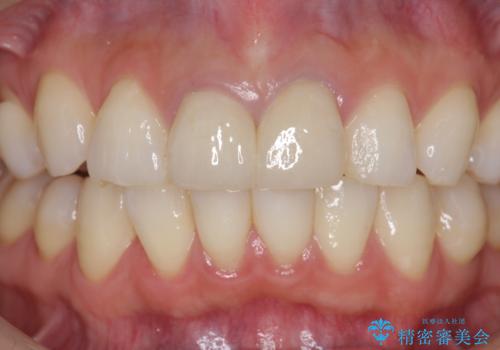

- 26.2万円(仮歯・ファイバーコア・ジルコニアクラウン×2)費用は治療当時の料金となります

今回は根尖性歯周炎に対する根管治療を行ったことで症状は改善し、快適に食事ができる状態へと改善しました。

セラミック治療の注意事項(リスク・副作用など)